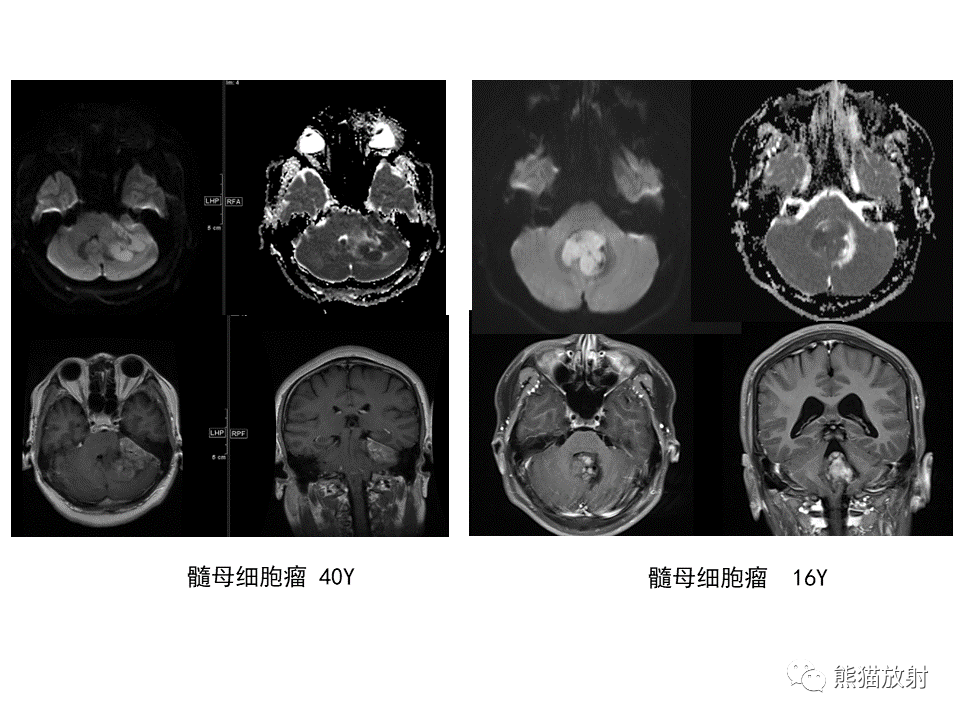

【PPT】小脑发育不良性神经节细胞瘤 VS 成人型髓母细胞瘤-4